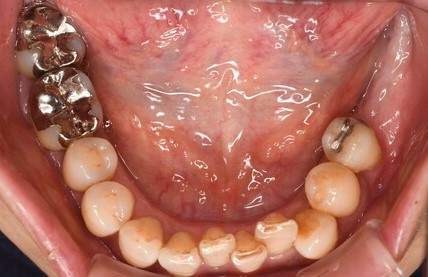

| 年齢 | 50代・男性 |

|---|---|

| 主訴 | 左上7番 左下5番7番 |

| 治療内容 | ・インプラント埋入 ※1:GBR(骨造成)・・・骨再生誘導法。骨の高さや厚みを人工骨や人工膜などを使用し再生する方法 |

| 治療費 | 合計:1,809,500円(税込) ■内訳 ・左上7番 ・左下5番7番 |

| 治療期間 | 左上7番約1年 左下5番7番約10ヵ月 |

| 治療方針 | 左上7番は昔他院で被せものをしており、被せものの中が歯ぐきの中まで虫歯になっていたため抜歯せざるを得ない状態だった。抜歯と同時に骨造成を行い、骨が出来るまで4ヵ月待ってからインプラントを埋入した。 ※2ポンティック・・・歯のない部分を補うダミーの歯。 |

| 担当者所見 | 元々金属の被せものが多く入っていたため、2次カリエス※3が多かった。今回は金属ではなく、ジルコニアを使用し、2次カリエスにならないよう、患者様にはブラッシング指導とメンテナンスの重要性をお伝えした。 ※3二次カリエス・・・詰め物や被せものを入れた歯が虫歯になること。 |